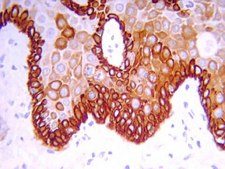

抗细胞角蛋白 19 抗体(克隆 RCK108) 是针对细胞角蛋白 19 的抗体,用于FC、WB、 IC、IH(P)。

免疫组化:1:100-1:200;冷冻和石蜡包埋的组织切片(胰蛋白酶或胃蛋白酶处理后)。

细胞角蛋白19.MAB3238 与腺上皮细胞和大多数癌细胞反应。不与肝细胞和肝癌细胞反应。